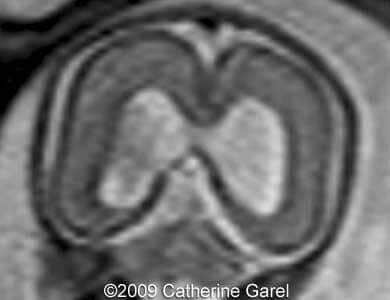

Images 9,10: Images 9, 10 show a fusion in the posterior frontal and parietal regions, indicated by arrows.

Case262_9a

Case262_10a

Images 11,12: Images 11,12 show the neuropathology specimen, sliced at the same plane is the MRI images above, see arrows.

Case262_11b

Case262_12a